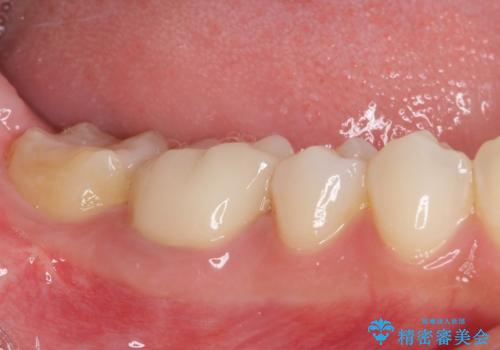

- 審美的ではない上の前歯とデコボコの下の前歯、歯茎が腫れている奥歯を気にして来院された患者様です。

根管治療の必要な歯がいくつかあるため、まずは根管治療を行い、その後インビザラインにて矯正治療を行うこととしました。

矯正治療後に前歯をセラミックブリッジに、奥の銀歯はセラミックインレーやPGAインレー(ゴールドインレー)にて補綴・修復治療を行うこととしました。

矯正治療により下顎前歯を整列させたため、上顎前歯のセラミックブリッジを補綴することで口元を少し下げることができました。